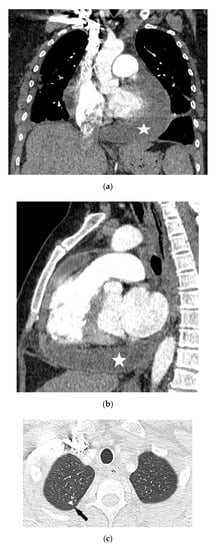

4.1.3. Chest Computed Tomography